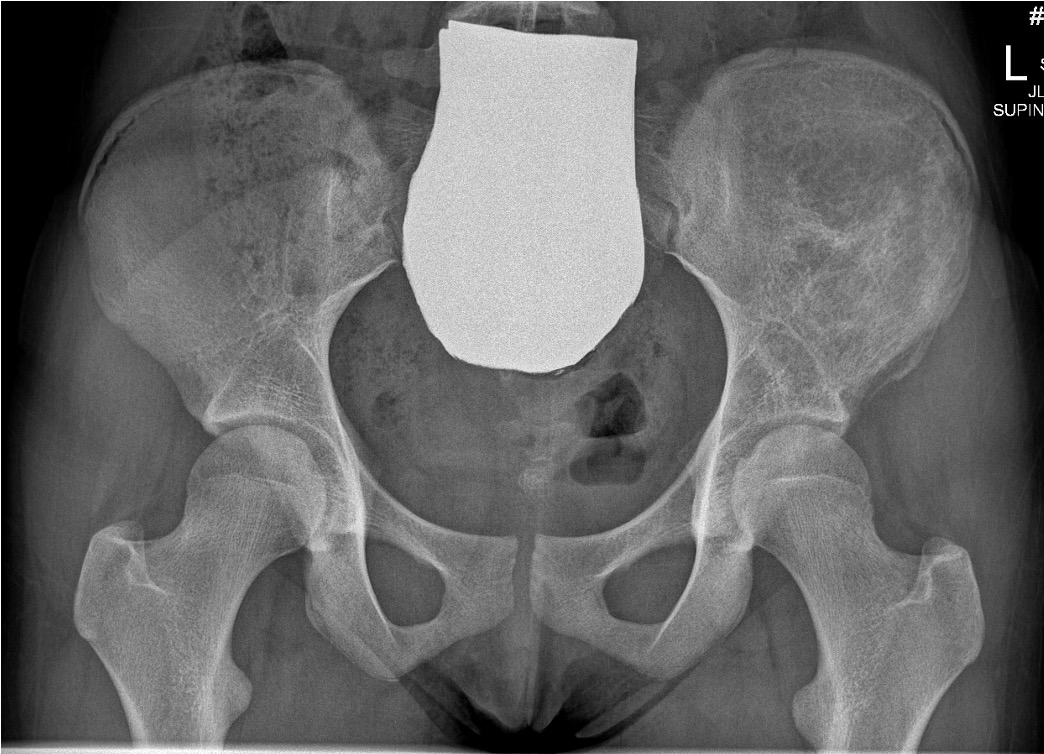

Ewings superior pubic rami